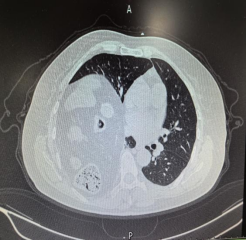

入院后完善胸部CT

结果显示右侧巨大膈疝(膈膨升?),右肾、胆囊、胃窦等多个腹腔器官都通过膈肌的“蓬松”缺损疝入胸腔,还压迫得右肺体积缩小、纵隔左移。为确保治疗万无一失,科室迅速组织心胸外科、呼吸内科、放射影像科、心血管内科、ICU、麻醉科等多科会诊,最终敲定手术方案。